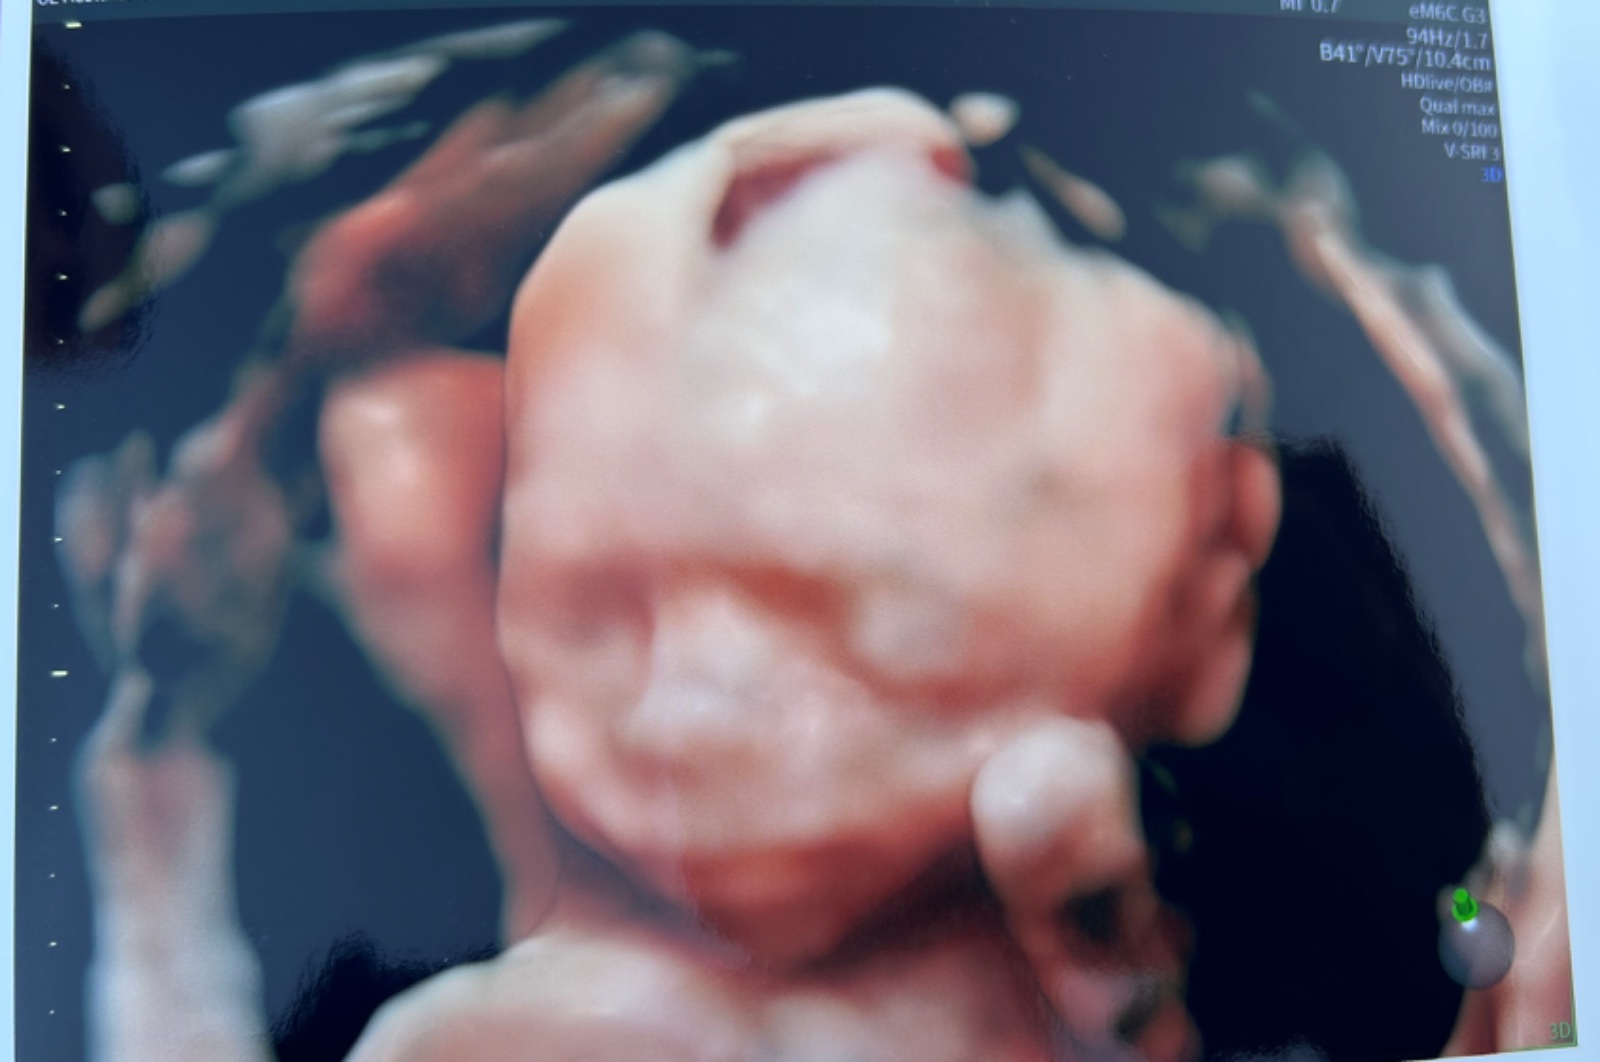

@nikadominikanika Prekrásny ❤️ 🙂

@babushkaem super 🙂 tak ti drzim palce .. dobré správy 😍 .. ja som už 6 mesiac, všetko v poriadku .. malý kope ako ďábel 😄 celkom to beží .. ani sa nenazdáme a máme ich tu 🙏🙏

@babushkaem nám sa malý skrýval u Grochalu :D ani fotky nemám, iba jednu haha .. kýval mi bruchom snažil sa ho otočil ale mal to krpec na saláme 😄

@babushkaem snaží sa aj o to na konci pán doktor .. pretáčal ma, horom dolom tlacil na brucho .. no bohužial maly nechcem :D